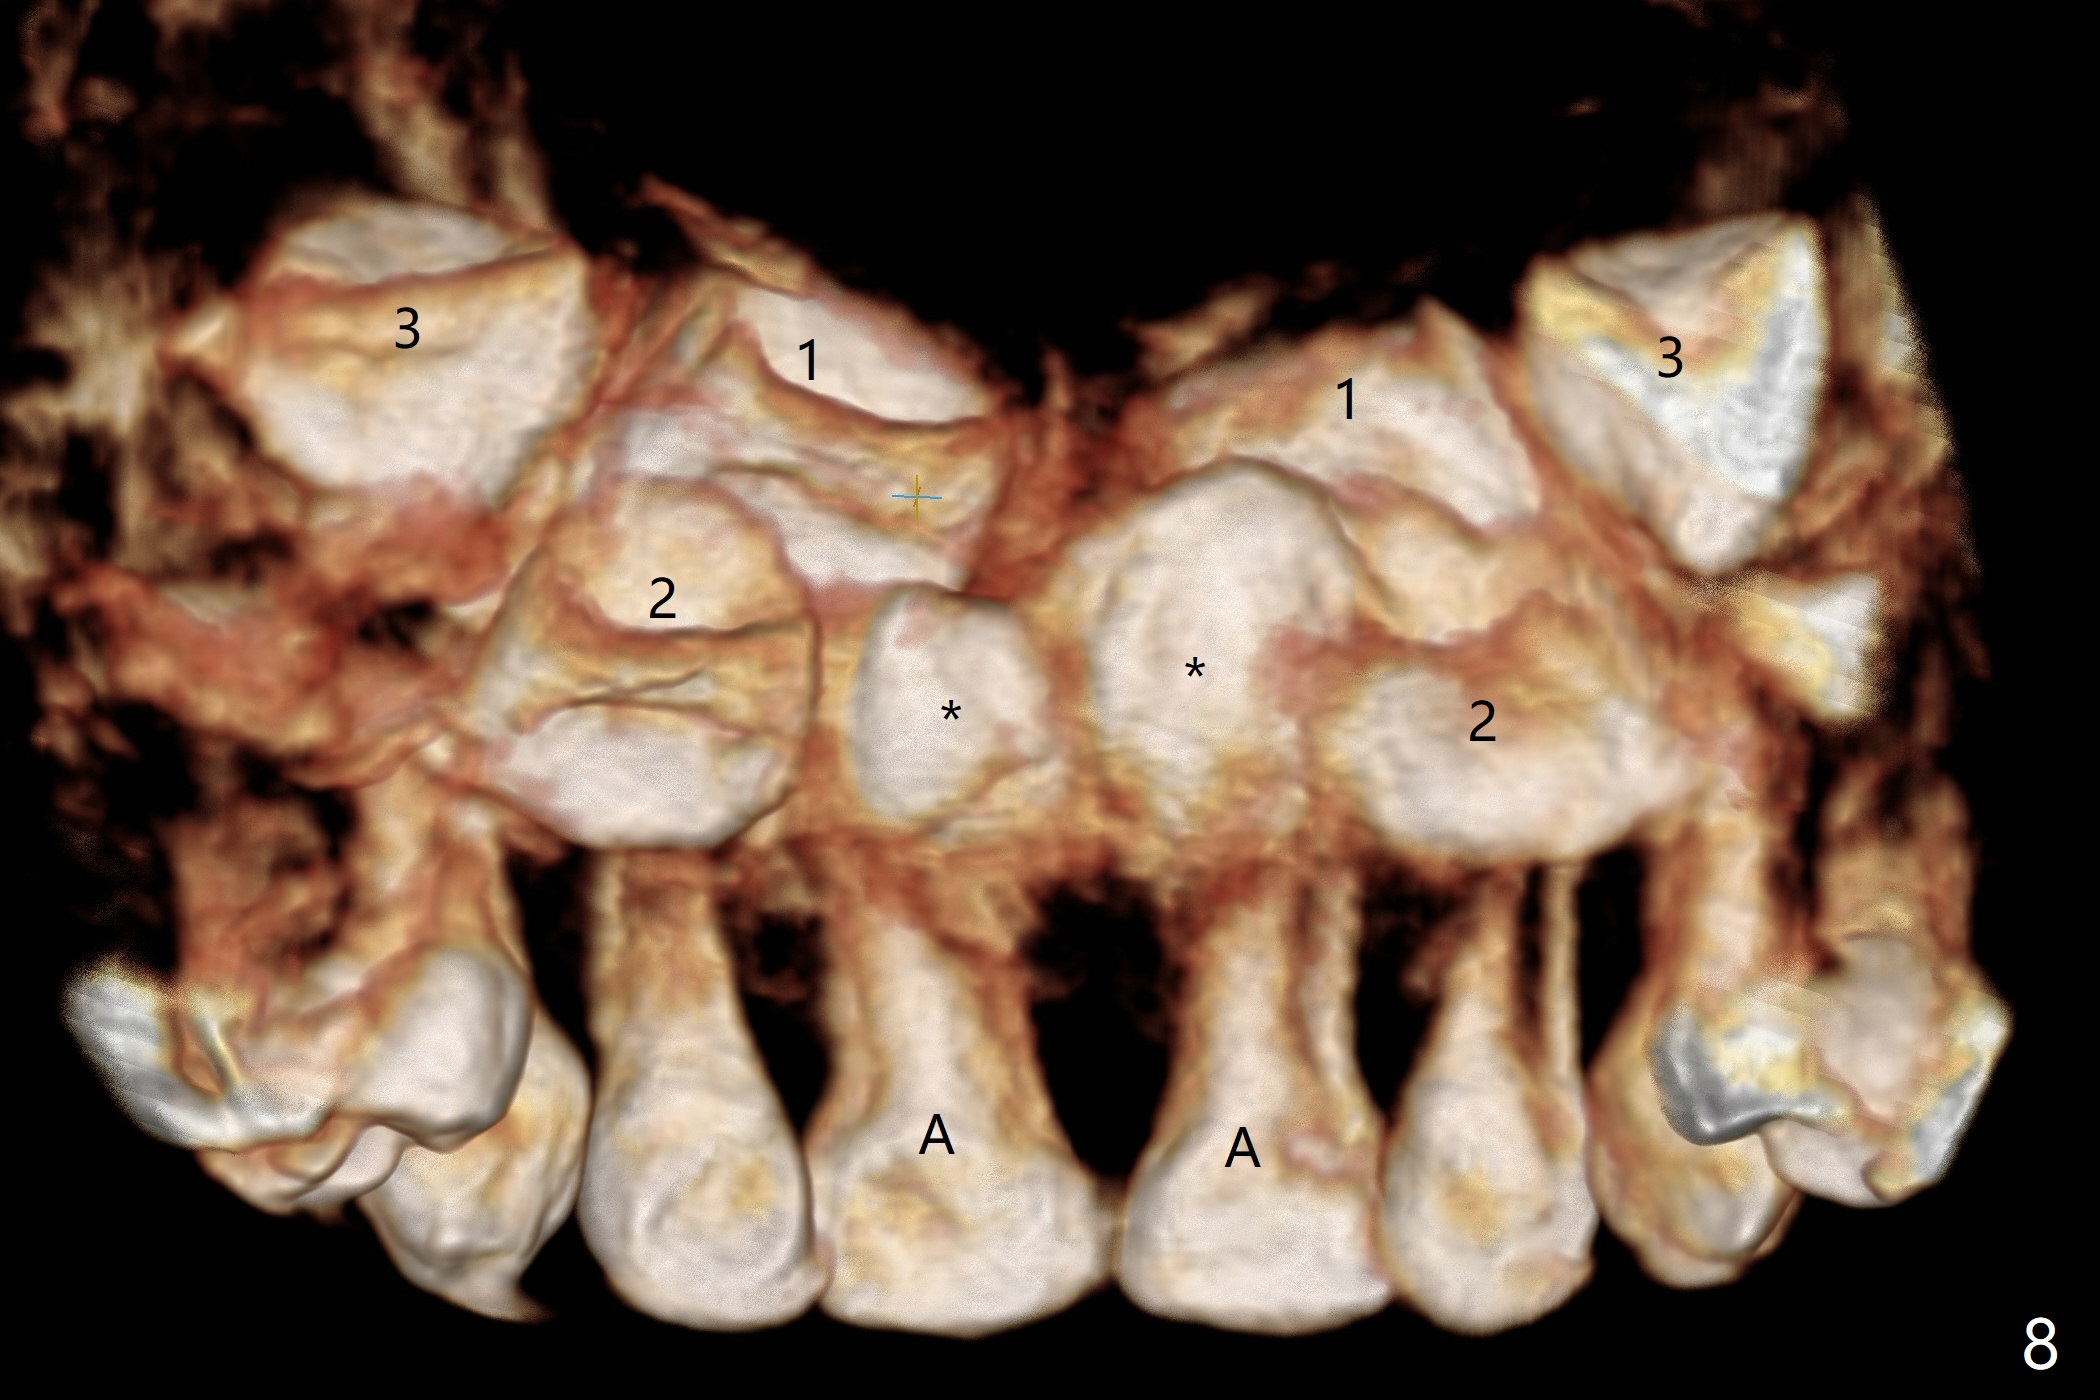

Reanalysis of 3 D images (Fig.7 (frontal view), 8 (posterior view), 9 (lateral view), 10 (lateral view with section) of CT taken 1 year 3 months earlier shows that the mesiodens (*) and the permanent lateral incisors (2) are palatal to the permanent central incisors (1) and canines (3) and the deciduous central incisors (A).  The supernumerary teeth do block the eruption of the permanent central incisors (Fig.10).